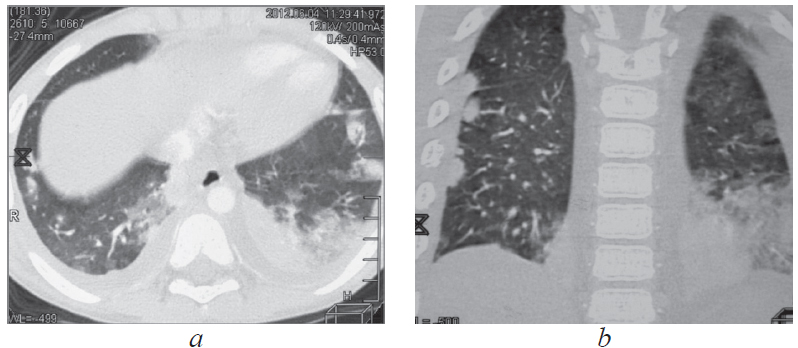

According to scientific research, malignant neoplasms in children are biomedical risk factors for the development of tuberculosis (TB). On the contrary, the occurrence of oncological disease in a child against the background of an existing tuberculous process is extremely rare. The combination of malignant neoplasm and tuberculosis creates difficulties in differential diagnosis, treatment of diseases, prevention of exacerbations and relapses. This article presents a clinical observation – the development of acute lymphoblastic leukemia (ALL) in a 6-year-old child against the background of TB of the intrathoracic lymph nodes during treatment. TB proceeded favorably despite multiple family contact in the child and resistance of Mycobacterium tuberculosis to anti-tuberculosis drugs in adult relatives of the patient. At the onset of ALL, bilateral pulmonary infiltrates and pleural effusion were observed, which were not associated with TB. Specific polychemotherapy for ALL and continued chemotherapy for TB led to the cure of two diseases. Supportive cytostatic and immunosuppressive therapy for ALL required periodic courses of anti-relapse anti-tuberculosis therapy for 5 years. After 10 years of observation, the child is healthy. Thus, the possibility of a rare in clinical practice combination of TB and ALL in children should be taken into account in the diagnosis and treatment of these diseases. During courses of immunosuppressive therapy for ALL, there is a risk of reactivation of TB. It is necessary to recommend long-term observation of such children by a phthisiatrician and an oncologist to prevent recurrence of both diseases.